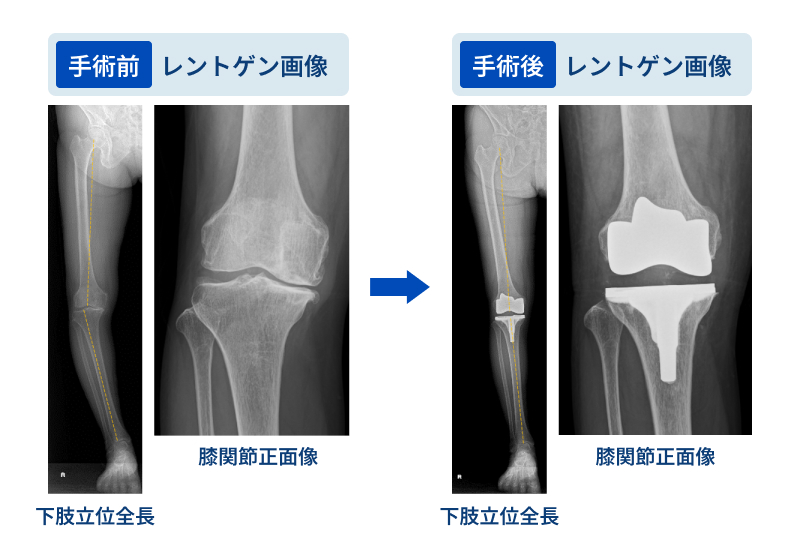

人工膝関節全置換術(TKA)は、中期から末期の変形性膝関節症に対して行う、最も標準的かつ効果的な治療法の一つです。

変形性膝関節症とは、膝関節の軟骨がすり減ることで炎症が起こり、痛みが生じる病気です。加齢や肥満などが主な原因で、進行すると膝の変形が進み、歩行や日常生活に大きな支障をきたします。(日本整形外科学会「変形性膝関節症」)

実際の手術では、傷んでボロボロになった大腿骨(太ももの骨)と脛骨(すねの骨)の関節表面を取り除き、金属やポリエチレンなどでできた人工関節に置き換えます。

手術後は翌日よりリハビリテーションを開始し、元々の歩行能力にもよりますが、術後2週から4週間程度での自力歩行での退院を目指します。

手術により頑固な膝の痛みが大幅に改善や関節機能の向上が期待できます。適切なリハビリテーションをする事で歩行能力が回復し、日常生活の質(QOL)が向上します。